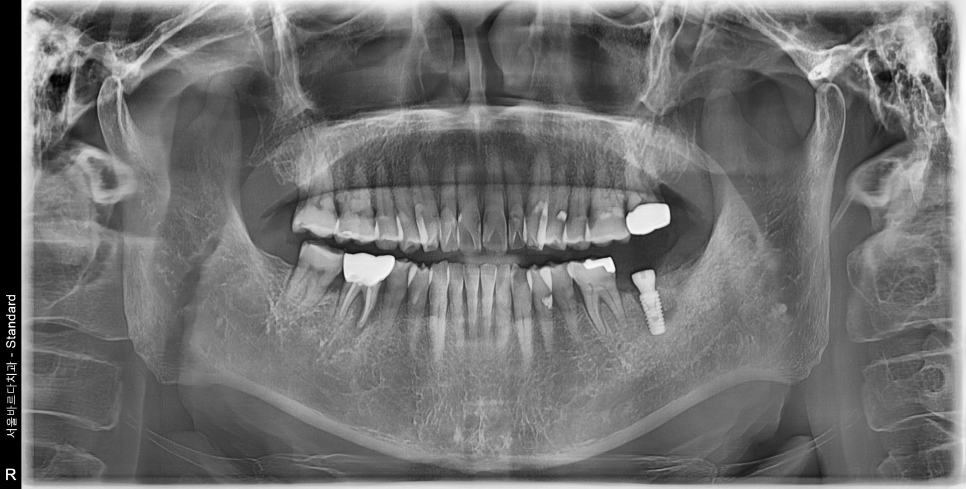

(이랫던 치아가... 30분이 지나면..)

요렇게 바뀝니다.

CT상으로 봐도 잘 들어갔군요.

주변부 뼈의 양도 골질도 매우 괜찮습니다.

다음 내원때는 먼저 심었던 임플란트에 상부 보철물을 셋팅하여 드렸습니다.

위 케이스와 같이 가용할 수 잔존골이 충분한 상태라면

임플란트는 2개월이면 가능합니다.